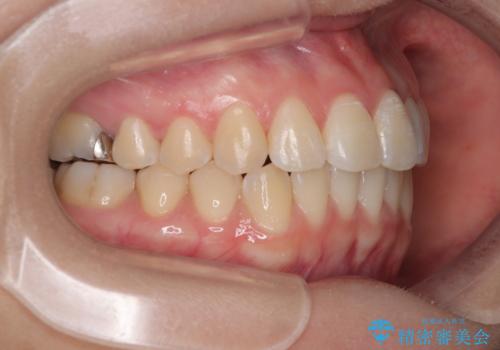

治療方法としては、装置の目立ちにくさと費用面のバランスを考慮して、プラスチック製のクリアブラケットとメタルワイヤーを組み合わせた矯正装置を使用することにしました。

また、上顎前歯の重なっていた部分にはむし歯が見つかり、治療中に適切な処置を行っています。